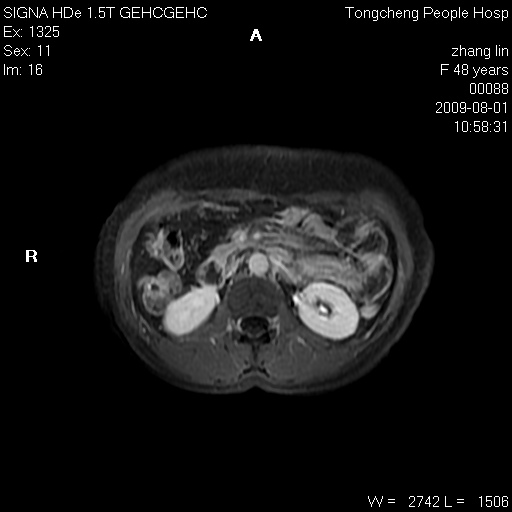

女,48岁。健康体检,彩超发现右肾占位性病变。平素健康。

临床诊断:右肾占位性病变,性质待定(囊肿?肿瘤?)。

上中腹部mr平扫+增强扫描,图像如下:

右肾上极见一类圆形病灶,t1wi呈等信号t2wi呈等高混杂信号,三期增强无强化,边界清---考虑囊肿出血。

同反相位均表现为等信号,病变无强化,考虑含蛋白的囊肿可能,弥散加权相或许有些帮助,